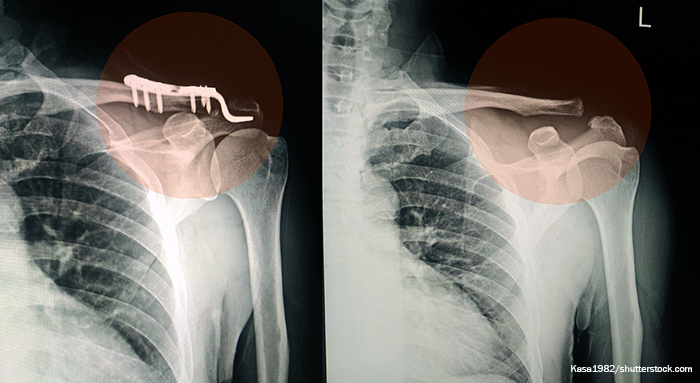

fractured clavicle

Dr. Robert Zura, Professor and Chair of Orthopaedic Surgery at LSU Health New Orleans School of Medicine, was part of a research team reporting that not only may opioid use increase the risk of bone fractures, but opioids may also impair healing. The authors also question their effectiveness in controlling pain. Dr. Zura is a coauthor of the “Article in Press” available online in the journal, Injury.

The team studied 309,330 of the 18 most common bone fractures, as well as medication use, including antibiotics, anticoagulants, diabetes medications, osteoporosis medications, cardiac medications, diuretics, immunosuppressants, steroids, anticonvulsants, and non-opioid analgesics in addition to opioid analgesics. They found that opioid medications as a class significantly increased the risk of fracture nonunion following both acute and chronic administration.

“Chronic opioid use roughly doubled the risk of nonunion among all patients, and this effect was fairly consistent across all ages and both genders,” noted Dr. Zura.

The researchers report that Schedule II opioids, as a group, create a greater nonunion risk than non-opioid analgesics. Certain of these medications produce a significant risk, including acetaminophen/oxycodone, hydromorphone, acetaminophen/hydrocodone, oxycodone and meperidine. Of the Schedule III-V opioids, tramadol and naloxone/pentazocine were also associated with increased risk. Acetaminophen/codeine and buprenorphine were not associated with increased risk of nonunion. Prescription NSAID use also increased the risk of nonunion among chronic users.